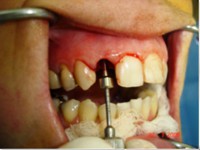

- Extração imediata

- Implante imediato

- Carga imediata

- Aplicação da cerâmica de baixa fusão direto sobre o pilar